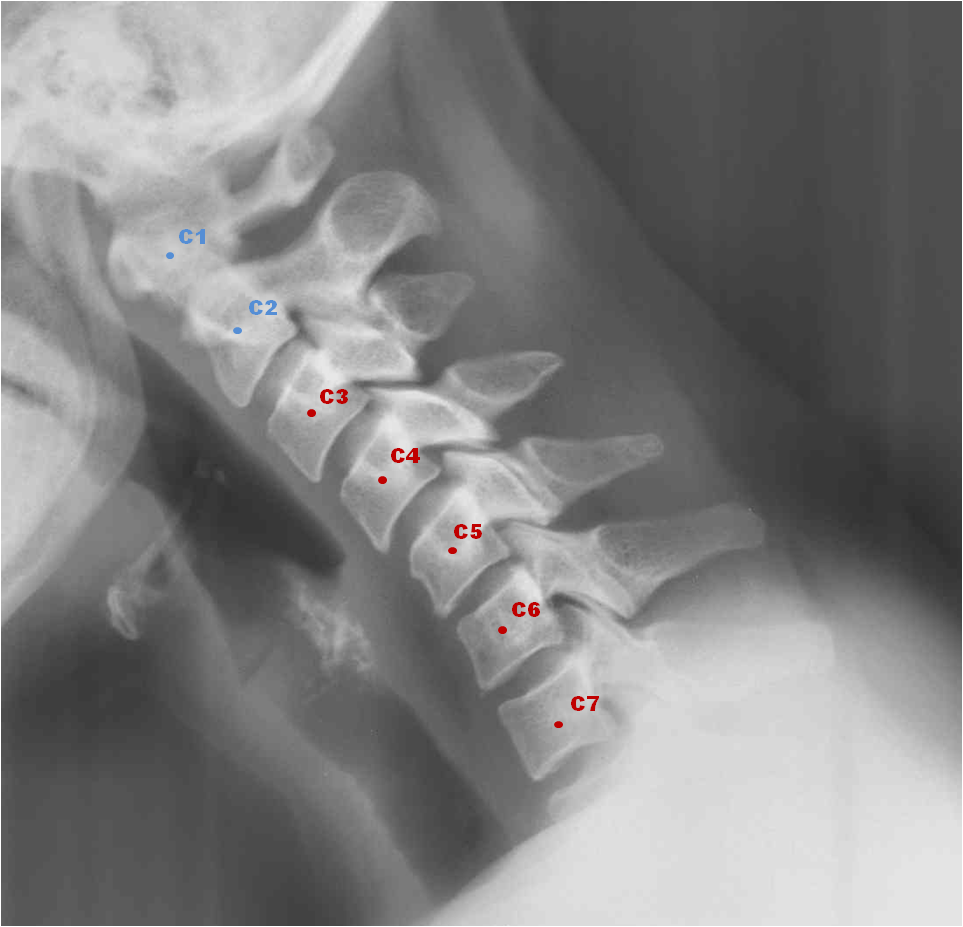

Группа UC Berkeley Embodied Dexterity Group придумала новое крутое носимое роботизированное устройство под названием Dorsal Grasper. Он предназначен для людей с повреждениями спинного мозга в шейных позвонках C5-C7.

Эти травмы затрудняют захват кистью предметов, но не приводят к полному отказу от движений запястьем. Многие люди используют технику, называемую тенодезным хватанием, когда вы держите запястья вытянутыми, чтобы сомкнуть пальцы. Но этот метод не является достаточно прочным и гибким для повседневной деятельности. Большинство существующих вспомогательных устройств либо мешают работе рук, либо требуют инвазивного управления.